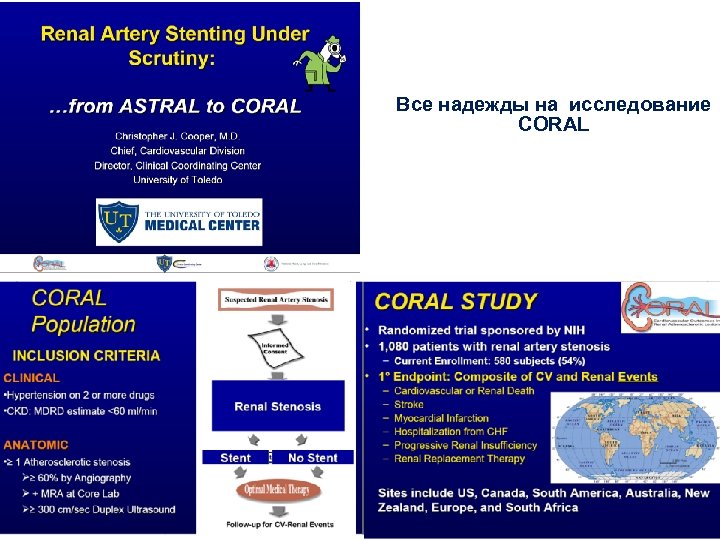

Все надежды на исследование CORAL

Все надежды на исследование CORAL